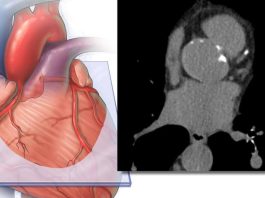

Donación de Órganos: ¿Donarías un órgano?, ¿recibirías uno?

¿Donarías un órgano?, ¿recibirías uno?

¿Eres donante de órganos?, ¿tu familia lo sabe?

¿Donarías tus órganos?, ¿y los de tu hijo o hija?

“Un día puedes ser...